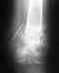

После перелома пятки прошло 8 месяцев.Беспокоит дистрофия икроножной мышцы,хромота, варус.

Предпагают артродез подтаранного сустава,либо трехсуставной.Какой прогноз в моём случае?Останется ли хромота и мышечная дистрофия?Если другие варианты?Мне кажется что кости невсе или неполностью срослись.

В общем, ситуация нередкая, действительно, при внутрисуставных переломах пятки иногда бывает целесообразен таранно-пяточный артродез. Без снимка предметно невозможно комментировать.